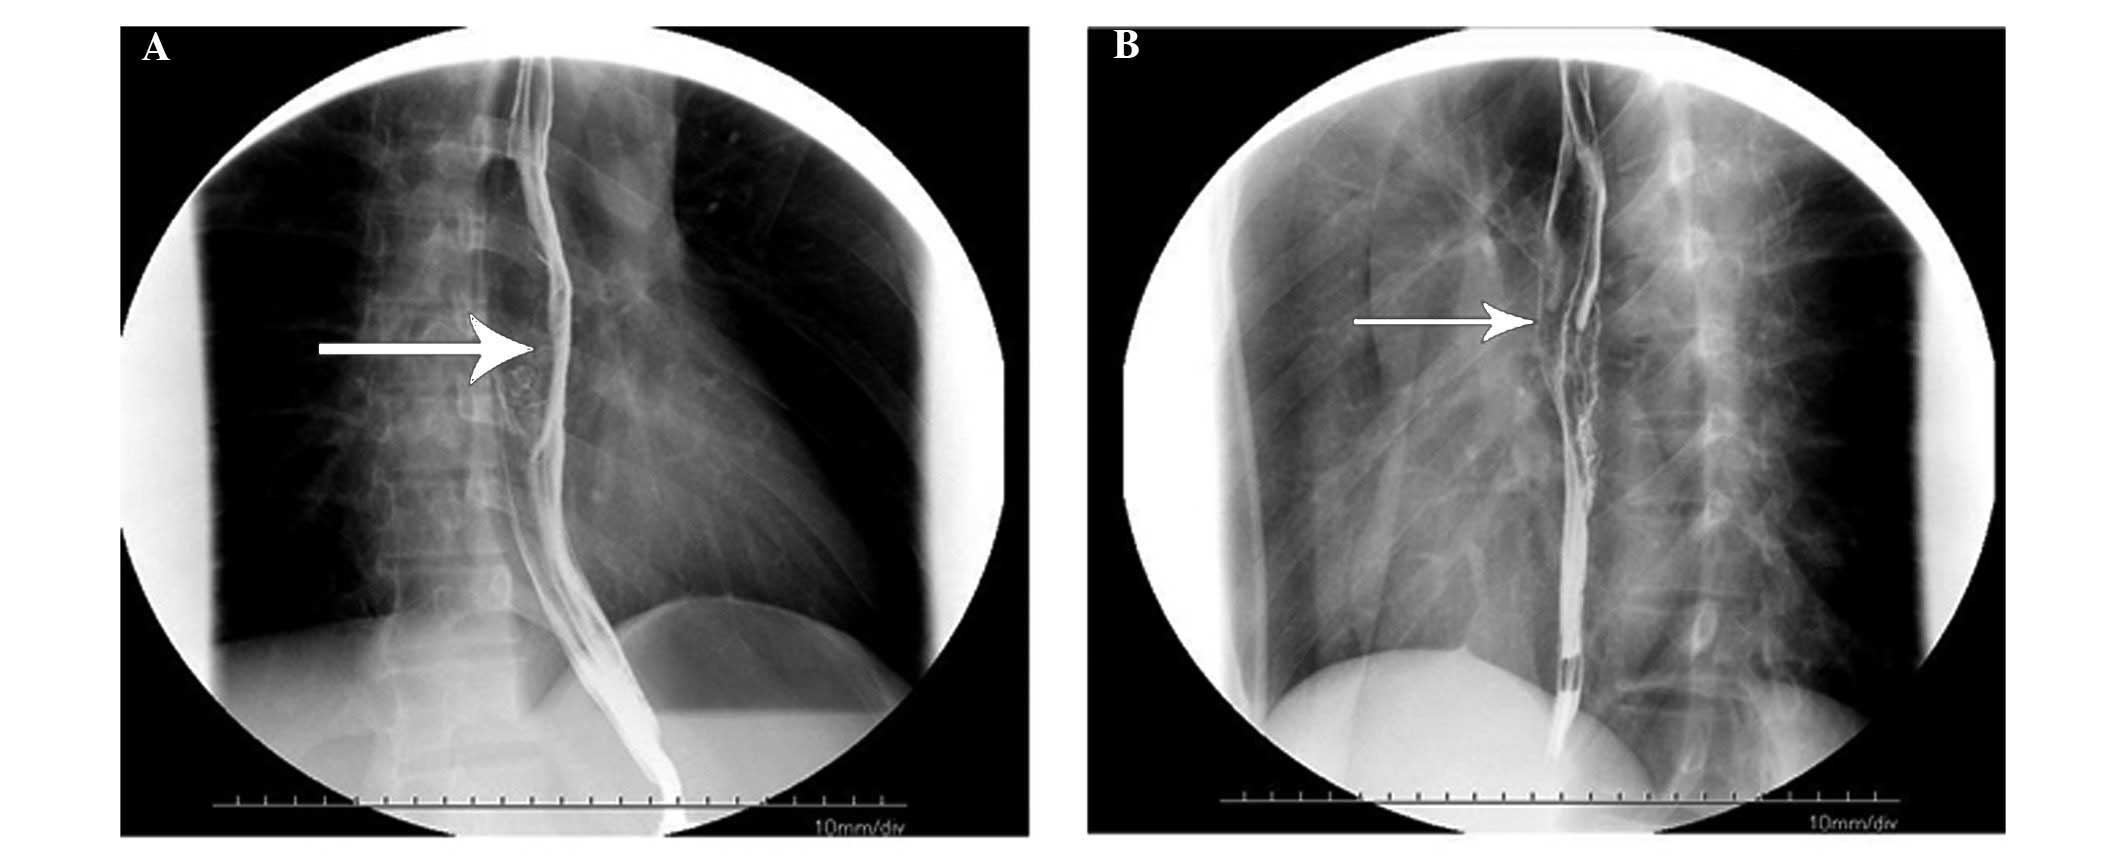

A 21-year-old man, who had been diagnosed in 2011 with nasal NK/T-cell lymphoma, was admitted to the Department of Oncology at Tai-He Hospital (Hubei, China). The patient was treated with 4 cycles of cyclophosphamide, vincristine, daunorubicin and dexamethasone (CHOP regimen), followed by local radiotherapy with 56 Gy in 26 fractions (2.15 Gy/fraction) of gross tumor volume. The patient remained in remission until April, 2014, when he was admitted with a 2-month history of discontinuous fever peaking to 39°C without an obvious cause, and difficulty in swallowing. The patient underwent an emergent esophagogastroduodenoscopy, which revealed an irregular mucosal elevation at a distance of 30–36 cm from the incisors. The mucosal surface was eroded and mildly indurated. A computed tomography scan revealed a mild thickening of the wall of the lower esophagus (Fig. 1). The barium swallow indicated slow passing of the barium through the lower esophagus (equivalent to the level of the thoracic vertebrae 7–9), with esophageal wall stiffness, mildly limited expansion and mucosal damage; the length of lesion was ~8.1 cm (Fig. 2). The patient reported no symptoms of cough, expectoration, hemoptysis or abdominal pain.